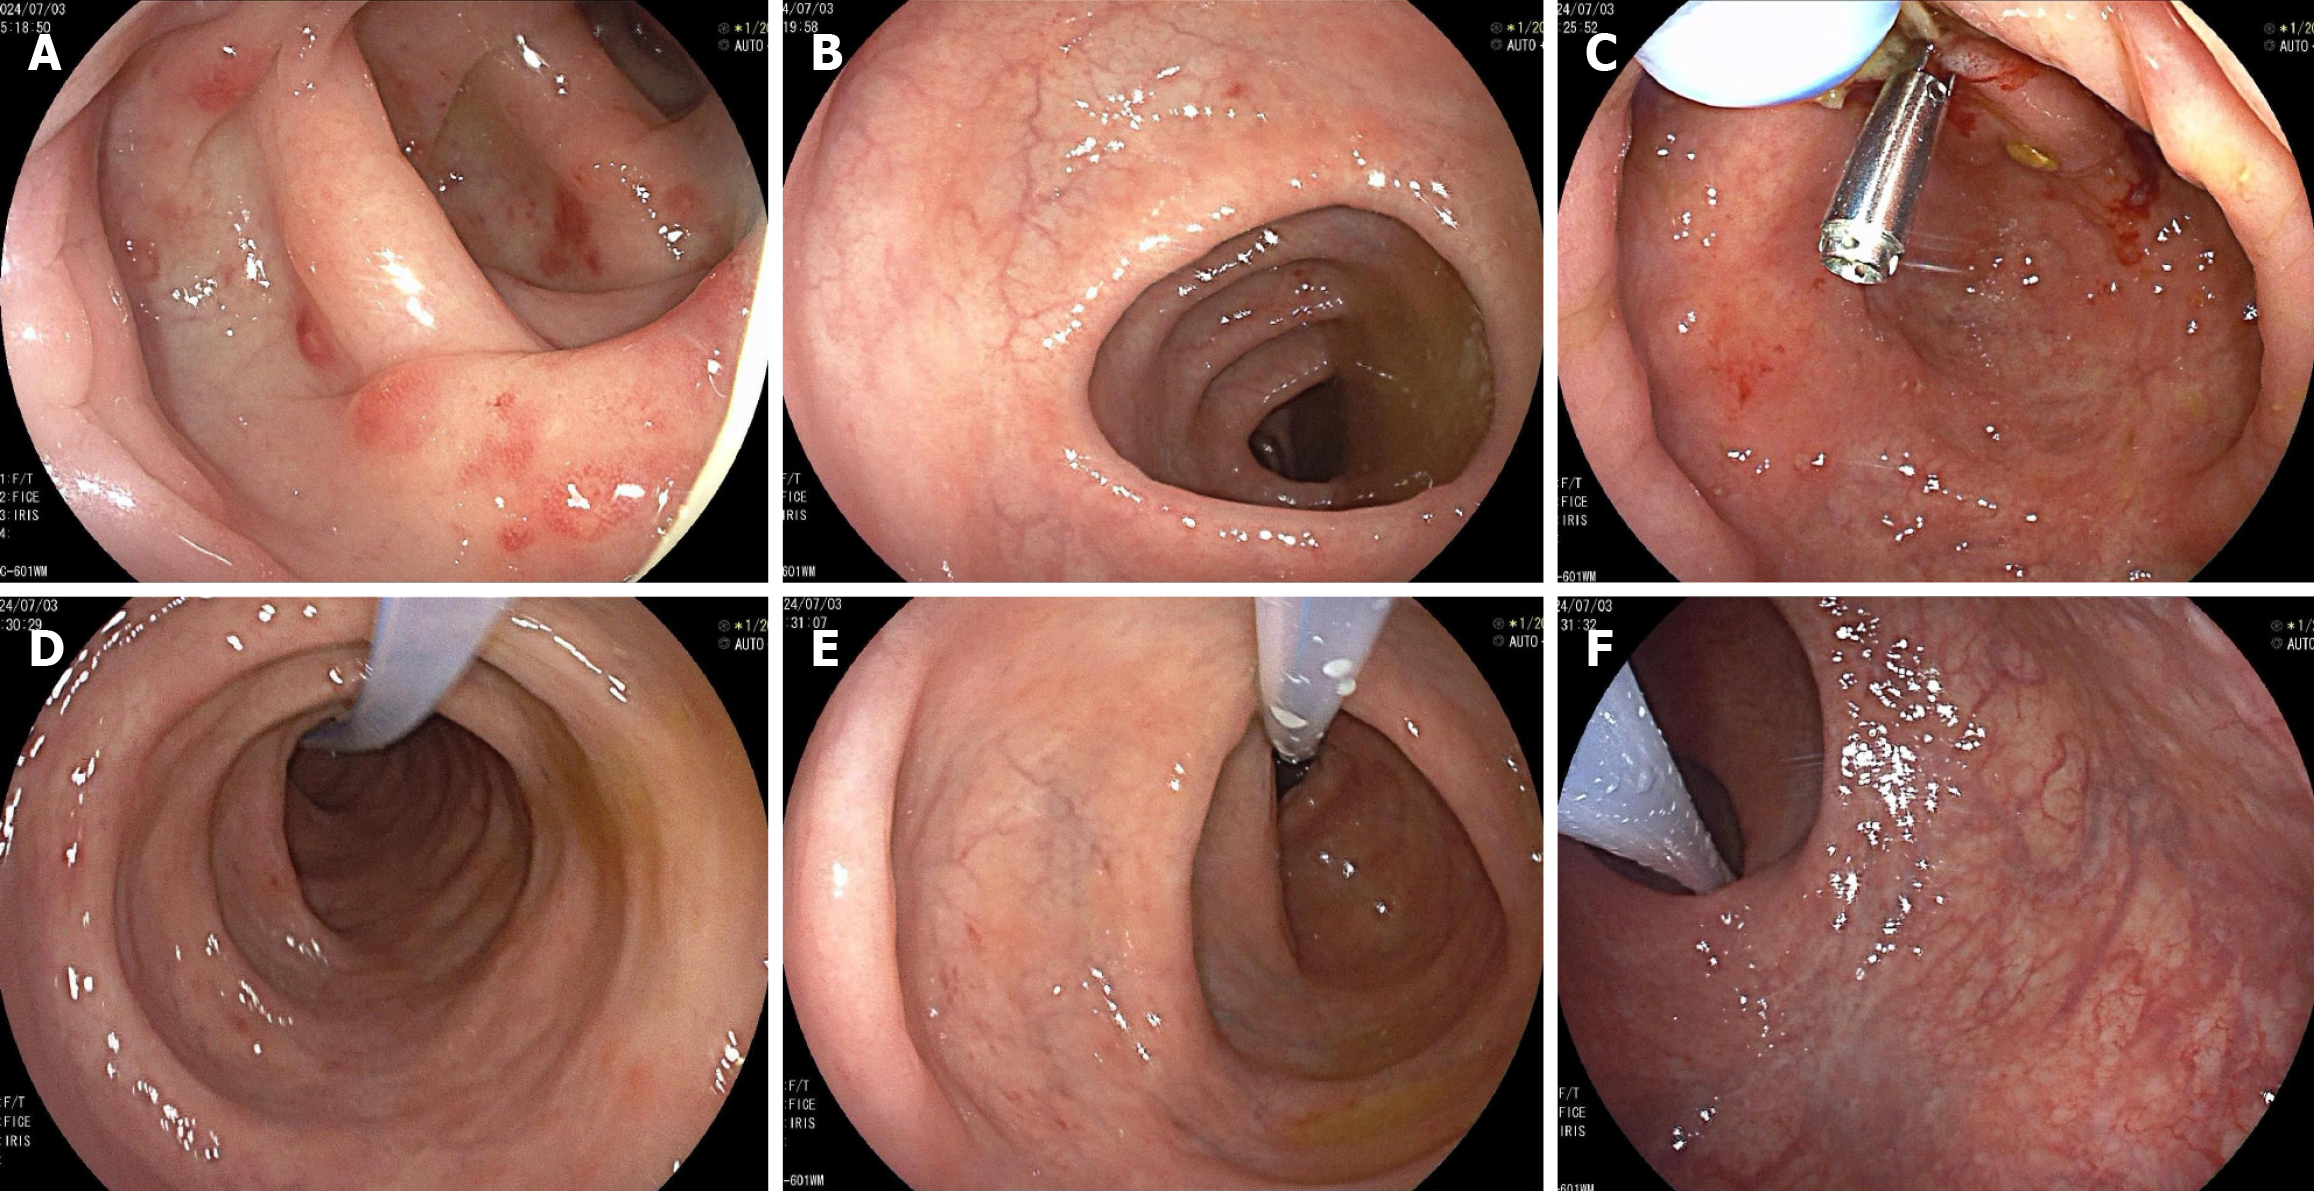

Figure 6

Figure 6 Enteroscopic presentation at the fifth fecal microbiota transplantation. Endoscopic fecal microbiota transplantation placement. Endoscopic presentation: Edema of the intestinal mucosa with multiple punctate erosions and blurred vascular texture. A: Transverse colon; B: Ascending colon; C: Cecum; D: Transverse colon; E: Descending colon; F: Rectum.

The patient’s bowel condition improved 1 month after the first FMT; the frequency of evacuation was 1-2 times a day, the stools were yellow, molded, and soft (Bristol 4 and 5), and there was an occasional feeling of incomplete evacuation. Although a few ulcers and tissue hyperplasia were still present in the patient’s oral cavity, the patient gained approximately 10 kg over the previous month. The patient underwent a second and third FMT (in September 2021 and March 2022, respectively) to maintain the therapeutic effect and was treated with thalidomide to regulate immunotherapy. A follow-up colonoscopy 9 months after the third FMT (Figure 5) demonstrated improved endoscopic findings compared to the previous procedure. In January 2024, the stool frequency was 2-3 times per day after an out-of-town business trip, with a thinner stool consistency (Bristol 6 predominantly) compared to the previous one. Concurrently, the patient developed progressive numbness in both lower extremities, whereas the oral ulcers showed gradual improvement and ultimately resolved. Following multidisciplinary consultation, the bilateral lower limb numbness was considered an adverse effect attributable to thalidomide, with a cumulative exposure of 28.75 g. Accordingly, thalidomide therapy was discontinued, and a fourth FMT was subsequently administered. The therapeutic effect was further consolidated by treating the patient with a fifth FMT in July 2024 (Figure 6). The pathological findings from the colonoscopic biopsy during the fifth FMT session demonstrated marked improvement in the lesion compared to previous assessments. This manifested as moderate-to-mild lymphocytic infiltration with mild atypia observed in the lamina propria (descending colon) and the muscularis mucosae. Concurrently, a repeat abdominal CT (Figure 7) scan revealed no enlarged lymph nodes in the ascending colon, sigmoid colon, or mesentery. At present, the patient’s diarrhea has significantly improved; his evacuation frequency is 1-2 times a day, his stools are yellow, molded, and soft (Bristol 4 and 5; with no black stools or fresh blood stools), and he shows no mouth ulcers (Figure 1B). The patient has gained significant weight since the start of FMT (Figure 8), from 60.9 kg to 85 kg, and his BMI has increased from 19.01 to 26.53. The patient also expressed a high degree of satisfaction with the treatment outcome. Clinically significant improvements were observed in both functional status and psychological well-being. The resolution of diarrheal symptoms has restored his ability to maintain a normal occupational and social routine, without disruptions to professional commitments or daily activities. Furthermore, the patient reported markedly improved mood and a positive outlook regarding future health prospects. No FMT-related adverse events have been observed since the initial FMT. As of the submission of this report, the patient continues to undergo monitoring and one intestinal bacterial transplant per year.

After multiple cycles of chemotherapy, the patient in this case exhibited a suboptimal therapeutic response, with persistent and clinically significant symptoms, including oral ulcers, diarrhea, and weight loss. Nevertheless, whether the ongoing inflammatory manifestations were primarily driven by intestinal microbiota dysbiosis or represented adverse effects associated with chemotherapy remains unclear. The patient received thalidomide to regulate immunity and inhibit inflammation, and an FMT procedure to remodel the intestinal flora. The number of oral ulcers decreased after the first FMT treatment, and the frequency of evacuation and the character of the stools improved. The endoscopic performance of the patient’s intestinal tract was significantly improved after the third FMT compared with the previous procedure. This was manifested by a decrease in intestinal mucosal edema and the disappearance of small focal ulcers. The segmental nature of intestinal lesions was no longer evident. After five courses of FMT, the number of evacuations and characteristics of the patient's stools returned to normal, oral ulcers disappeared, and the patient’s body weight increased by approximately 25 kg from that at the start of FMT. These results suggest that the effect of a single course of FMT had a limited duration and that multiple courses of FMT may be necessary. Moreover, the patient’s endoscopic findings changed after each course of FMT, as evidenced by decreases in congestion and edema of the intestinal mucosa, the gradual healing of the erosions and small foci of ulcers, and a gradual reduction in intestinal staging lesions, lending further support to the need for multiple courses of FMT.